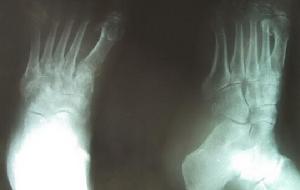

3、骨X線攝影:可發現骨萎縮像。